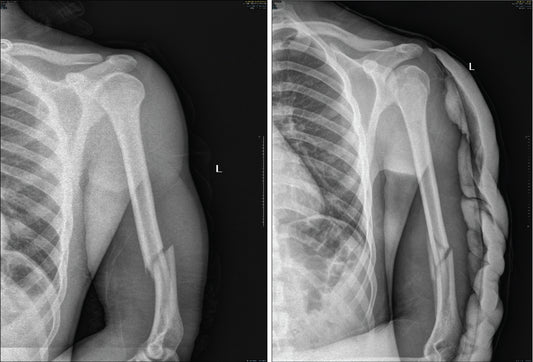

How to avoid arm breaks in Arm Wrestling

Avoiding arm breaks in arm wrestling is crucial for both safety and long-term health. While arm wrestling is a competitive sport, it can be dangerous if not approached with proper...